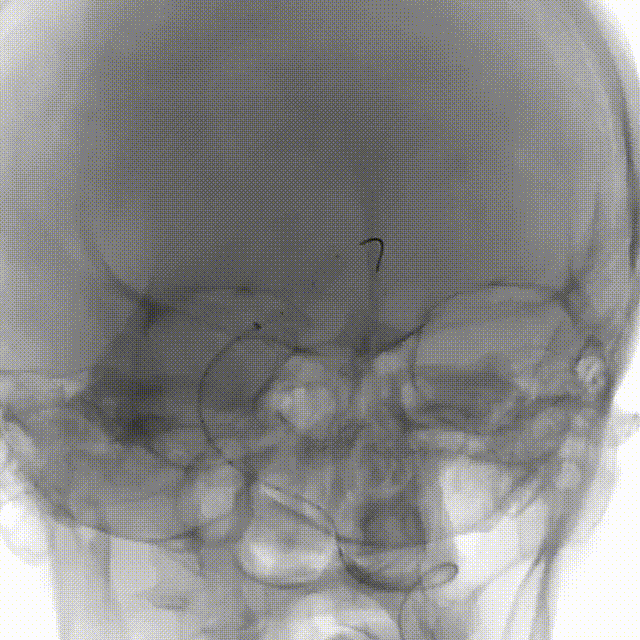

术后即刻造影: